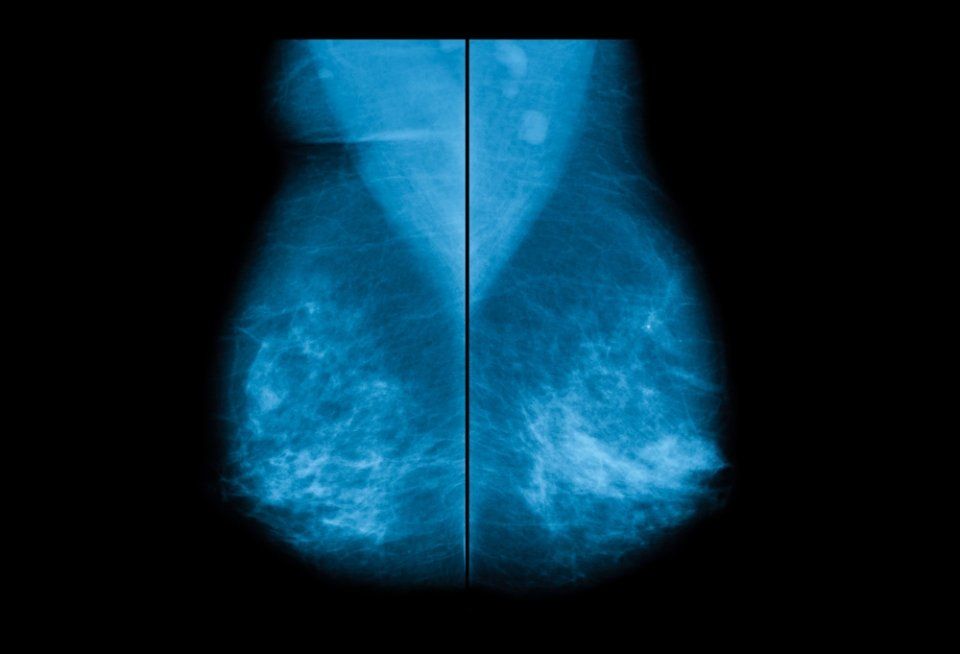

Mammografia bilaterale

Se hai bisogno di una mammografia a Caserta e dintorni, presso il nostro centro CE.DI.R. usiamo attrezzature che permettono di eseguire un controllo bilaterale completo: il metodo più indicato per individuare noduli, microcalcificazioni e altri segni di neoplasie.

Il test ha una durata variabile da 5 a 10 minuti, va eseguito in piedi, a seno nudo e con una mammella appoggiata su un apposito ripiano dove il radiologo potrà comprimerla. Il test è sicuro e senza controindicazioni.